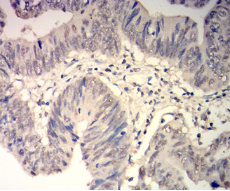

IHC    1/200-1/1000